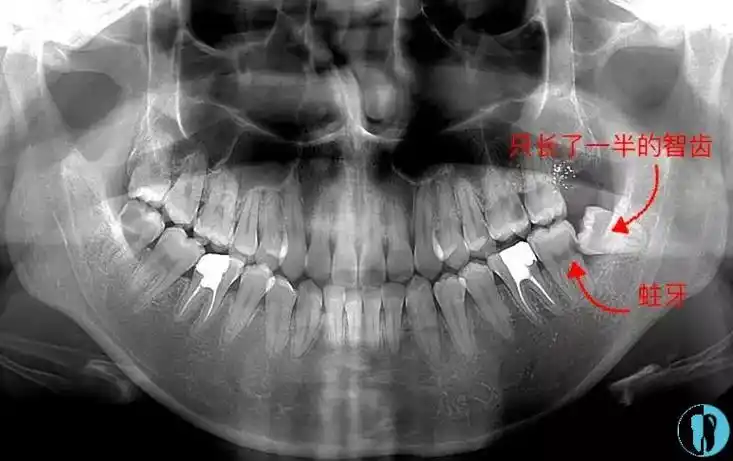

拔一颗尽头牙虫牙,用光了我一年的勇气!

智齿不痛就不用拔吗?看了这篇你就懂了!

扒一扒我上当了不该拔智齿的真相,不是所有的智齿一定要拔